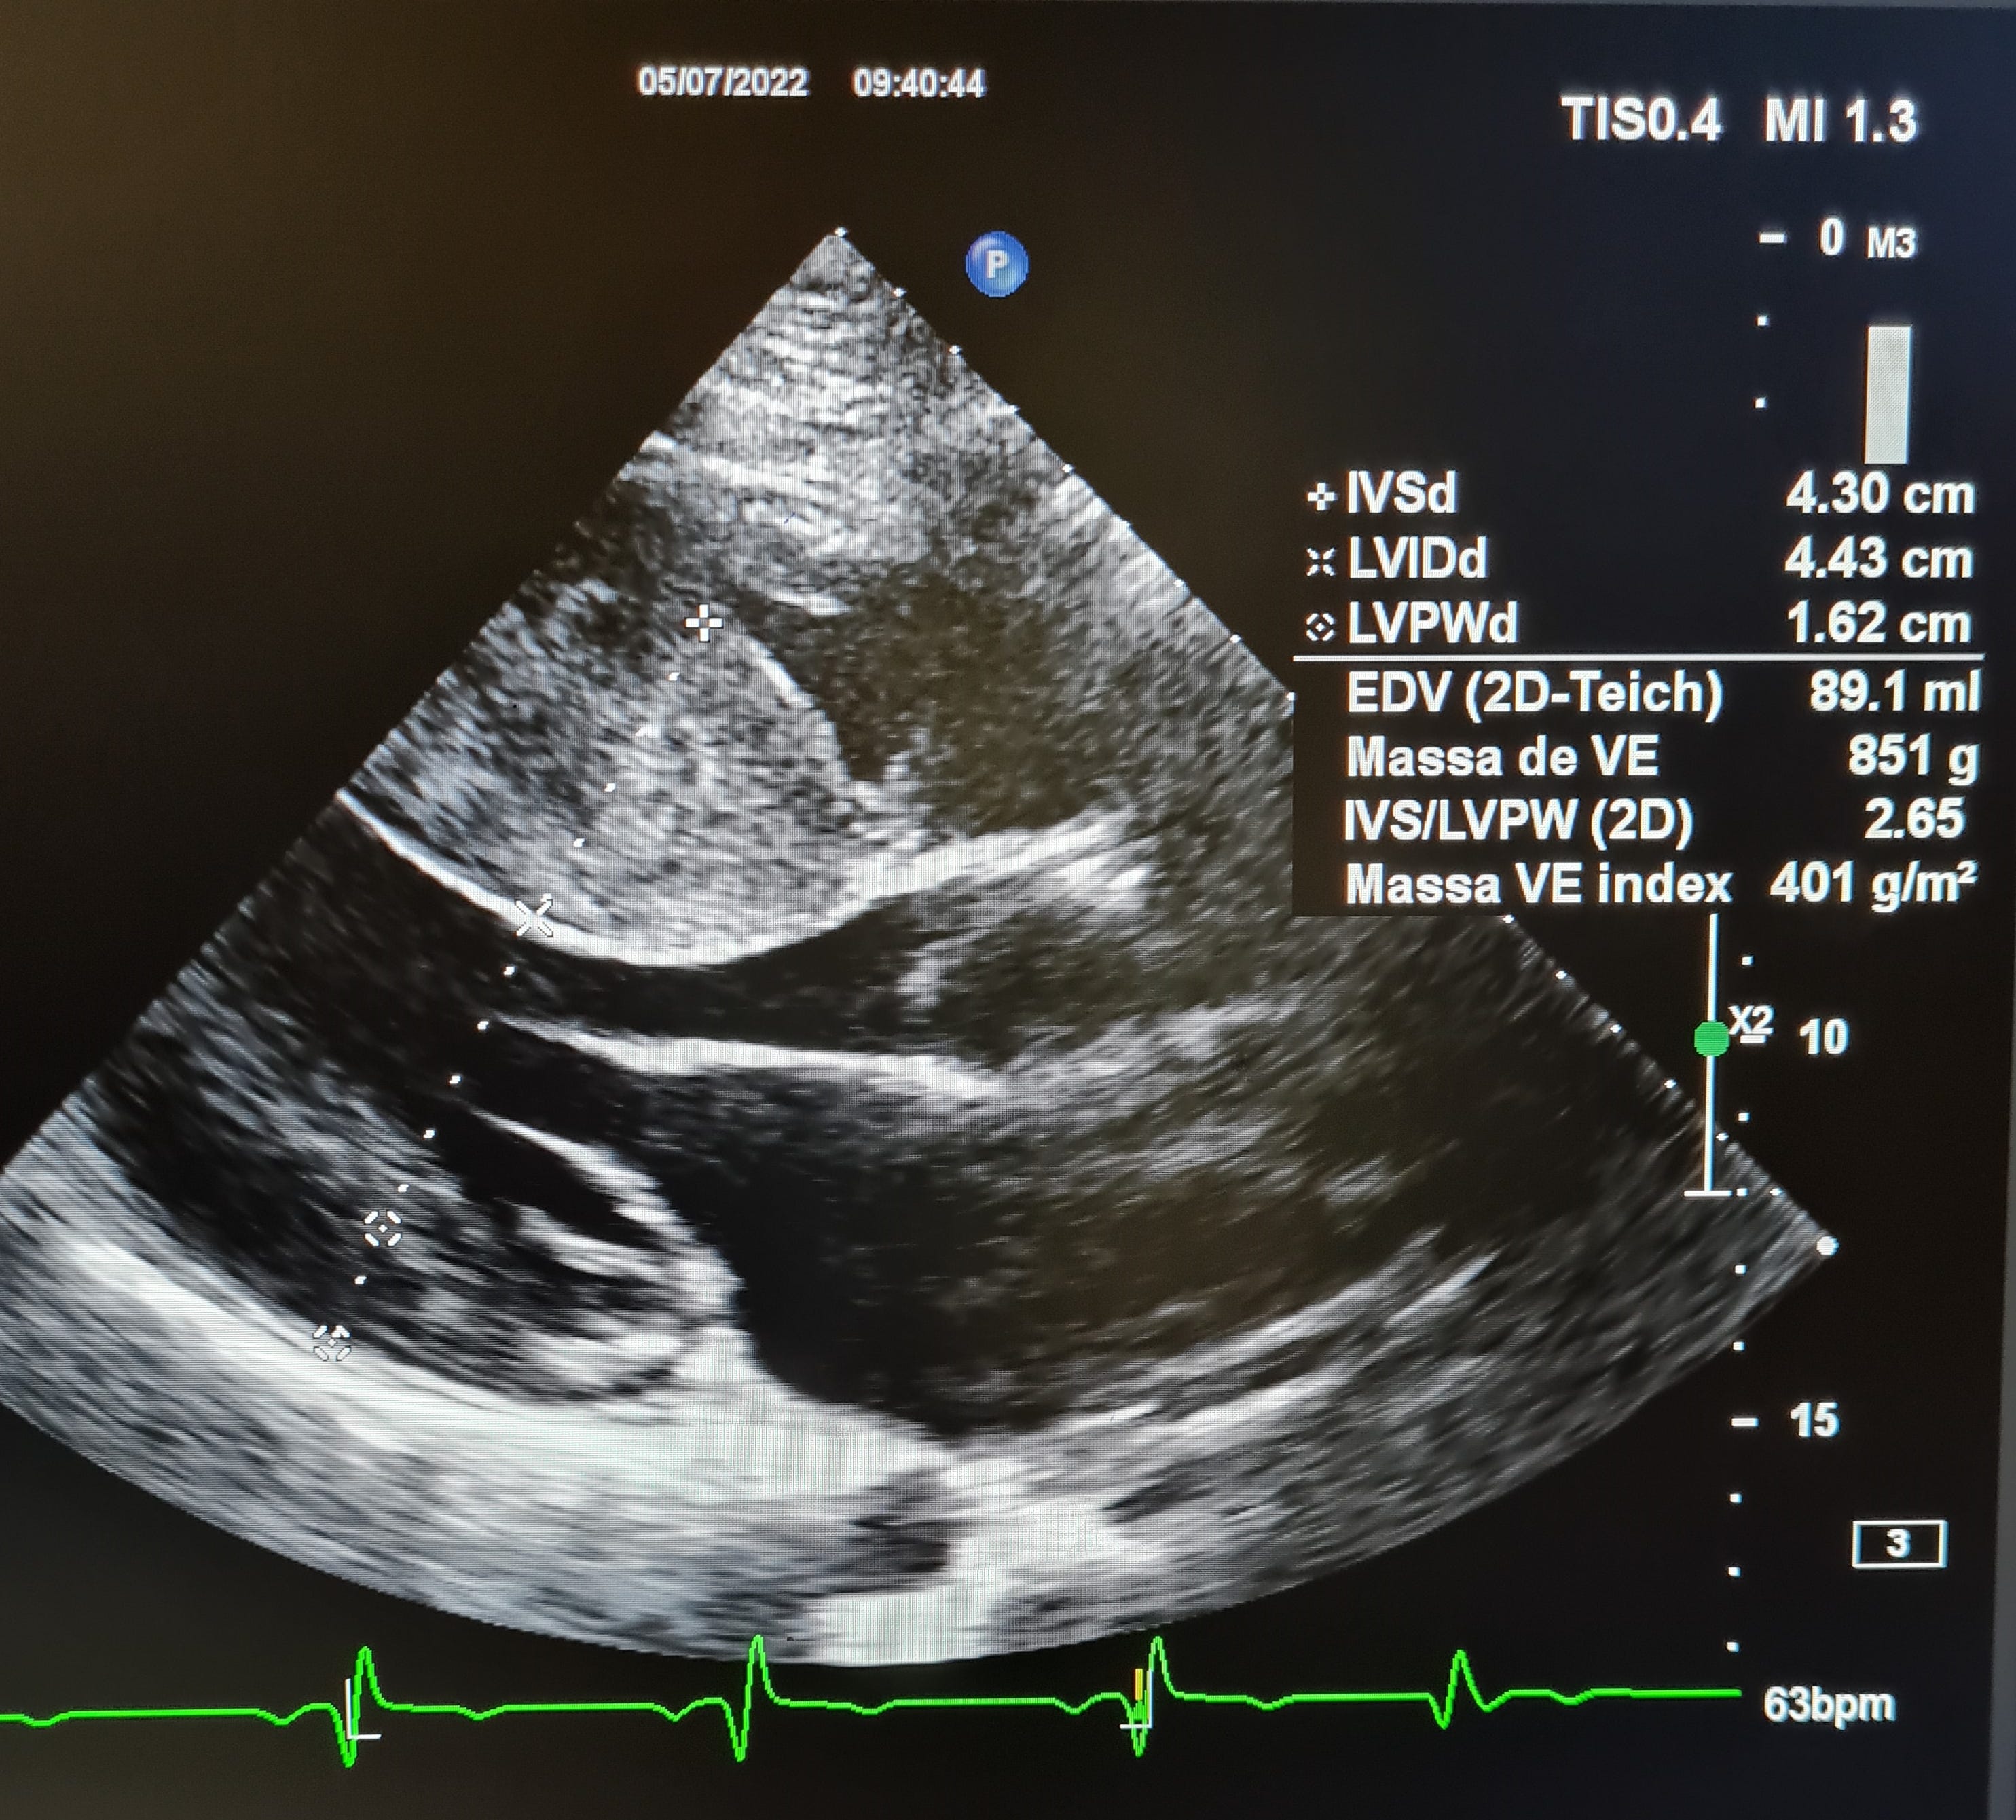

Imagem da Semana

Paciente do sexo masculino, 32 anos de idade, com miocardiopatia hipertrófica obstrutiva. Se já te mostramos nessa coluna os maiores átrios, segue um grande septo de 43mm com gradiente de 131 mmHg no repouso.